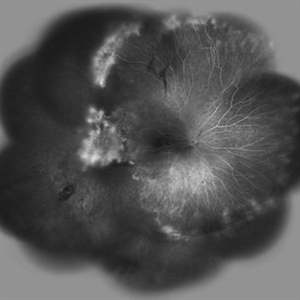

Behcet's Disease Behcet's DiseaseMar 13 2013 by Hamid Ahmadieh, MD Wide field FA of the right eye of a 23-year-old man with retinal vasculitis and branch retinal vein occlusion (BRVO) due to Behcet's disease . Photographer: Solmaz Shahmohammad, Negah Eye Center, Tehran Imaging device: Heidelberg Spectralis Condition/keywords: branch retinal vein occlusion (BRVO), retinal vasculitis